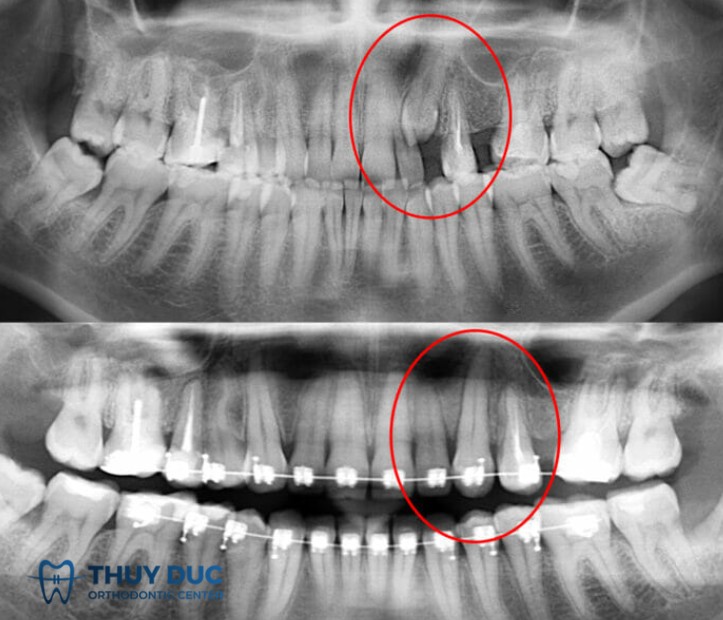

Vì vậy, phương pháp chẩn đoán chính xác nhất là chụp X-quang (thường là phim panorama hoặc phim cận chóp). Trên thực tế, rất nhiều bệnh nhân chỉ phát hiện mình có răng mọc ngầm khi đi khám và chụp phim để điều trị một vấn đề khác, ví dụ sâu răng, viêm nha chu hoặc chuẩn bị niềng răng.

Bác sĩ cần đánh giá toàn diện qua thăm khám lâm sàng, hình ảnh X-quang toàn cảnh hoặc CT Cone Beam để xác định vị trí và hướng mọc. Với răng có giá trị duy trì, đặc biệt là răng nanh hoặc răng cửa, ưu tiên là giữ và đưa răng về vị trí. Ngược lại, với răng khôn hoặc răng không cần thiết, nhổ bỏ thường là lựa chọn tối ưu nếu có nguy cơ biến chứng.

Với những răng có vai trò quan trọng như răng nanh hoặc răng cửa, đặc biệt ở người trẻ, bác sĩ thường chọn phương pháp bộc lộ răng và kéo vào cung hàm. Quy trình này bắt đầu bằng việc tạo khoảng trống trên cung răng bằng chỉnh nha, sau đó phẫu thuật bộc lộ thân răng và gắn khí cụ (móc, chain hoặc button). Lực kéo được áp dụng nhẹ nhàng và liên tục, thường kéo dài nhiều tháng cho đến khi răng về đúng vị trí.

Nhiều trường hợp phức tạp đòi hỏi sự phối hợp giữa bác sĩ phẫu thuật và bác sĩ chỉnh nha. Trước tiên, chỉnh nha được sử dụng để mở khoảng và tạo điều kiện thuận lợi cho răng di chuyển. Sau đó, phẫu thuật bộc lộ răng và gắn khí cụ kéo. Cuối cùng, chỉnh nha tiếp tục điều chỉnh toàn bộ khớp cắn để đạt kết quả tối ưu cả về chức năng và thẩm mỹ.